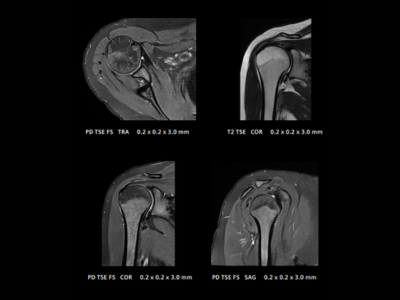

Shoulder Coil:

Articulating elements adapt to patient anatomy, delivering high-resolution images for shoulder diagnostics.